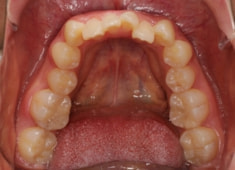

治療前